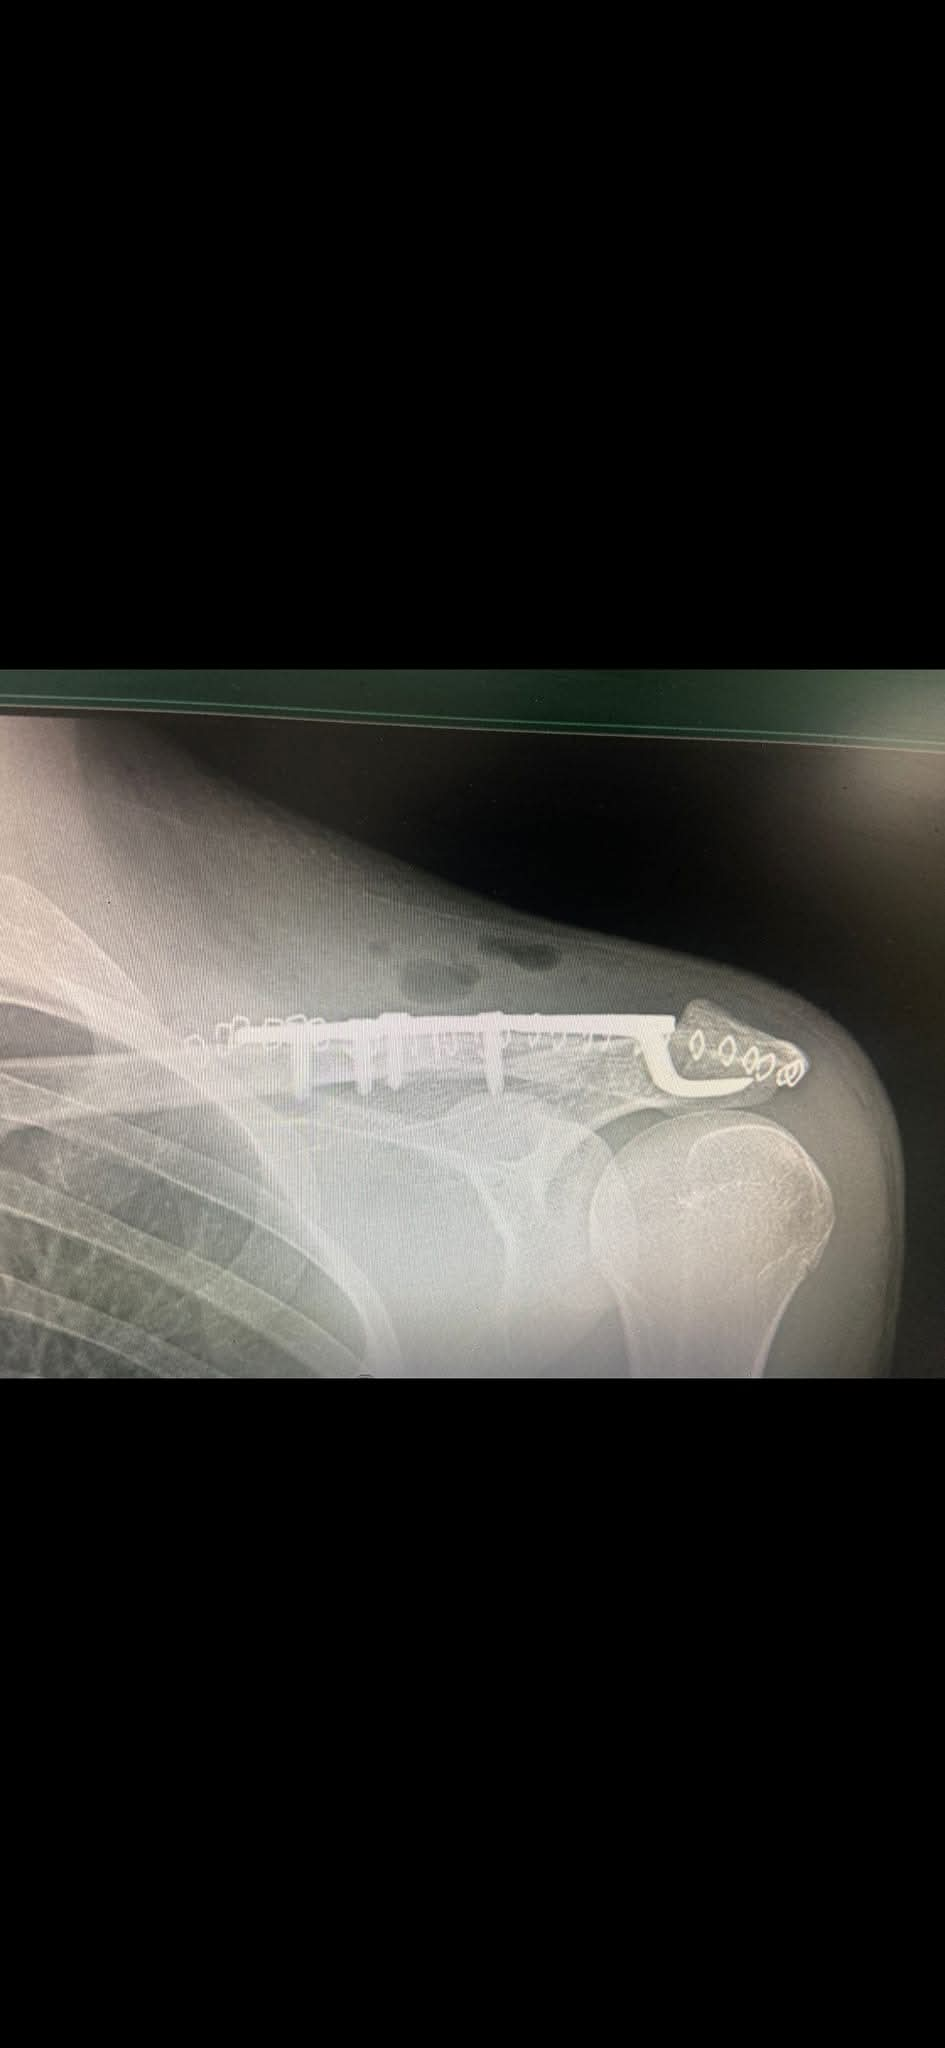

يقوم بعمليات تثبيت الكسور المعقدة بشكل طاريء وتبديل المفاصل بشكل مبرمج مما خفف على المواطنين البحث عن أسرة في مستشفيات مركزية رغم صعوبة عمليات العظام من الناحية التقنية في المستشفيات النائية إضافة الى استقبال اعداد كبيرة بالعيادات ومعالجة جميع المرضى بالطرق المثلى انه الدكتور الانسان البارع والمتميز يزيد البريزات طبيب العظام في مستشفى الاميرة سلمى / ذيبان عيادة العظام علماً بأنه كان مستشفى تحويلي منذ تاسيسه والدكتور البربزات وقبل اربع سنوات في عام 2020 منذ انتقاله للمستشفى يقوم بهذه العمليات ومن بينها عمليات نوعية لمرضى يعانون من كسور معقدة في الترقوة واجراء عمليات دقيقة ومعقدة لكسور لمرضى في مختلف أنحاء الجسم وعمليات تثبيت الكسور المعقدة وتركيب المفاصل وغيرها الكثير والديسك " وآلامه وتبعاته وعلاجه وإجراء عمليات معقده وصعبه.

وأجرى الدكتور البريزات عمليات كبرى في جراحة العظام والتي تحتاج إلى مراكز متقدمة ومتطورة. وكذلك العمل على تثبيت أغلب انواع الكسور بطريقة طارئة وتبديل المفاصل بطريقة مبرمجة بما يتناسب مع امكانات المستشفى والتي هي جزء من العمليات الدورية بمستشفى الاميرة سلمى في ذيبان والتي تخفف العبئ على المستشفيات المركزية وعلى المواطن في آن واحد.

وعبر كثير من المرضى وذويهم عن عظيم شكر هم وامتنانهم للدكتور البريزات على ما بذله ويبذله من جهود كبيرة واستثنائية في تعامله مع المرضى والمراجعين ومتابعته الحثيثة لهم والاطمئنان عليهم والتي تكللت جميعها بالنجاح وله الدور الكبير برفع كفاءة قسم العظام بالمستشفى بشكل عام والذي أصبح متطوراً بالقيام بالعمليات مثل تثبيت الكسور المعقدة و تركيب المفاصل و غيرها.